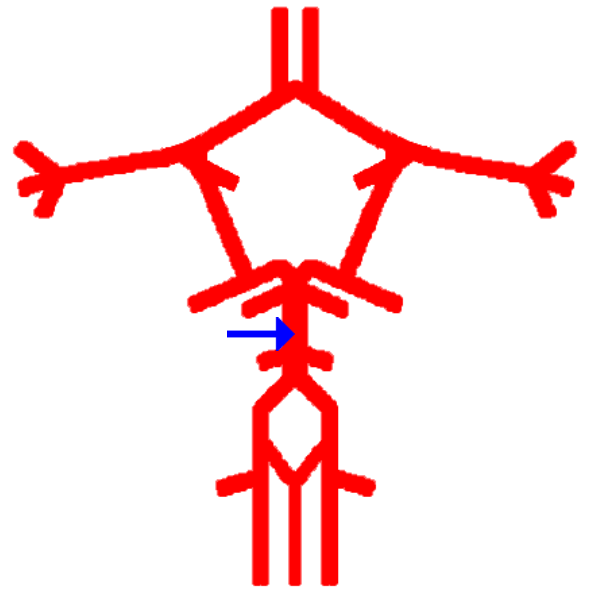

What is this?

Anterior cerebral artery

Label this cerebral artery

Basilar artery

Label this cerebral artery

Anterior communicating artery

Label this cerebral artery

Middle Cerebral Artery

Label this cerebral artery

Posterior Cerebral Artery